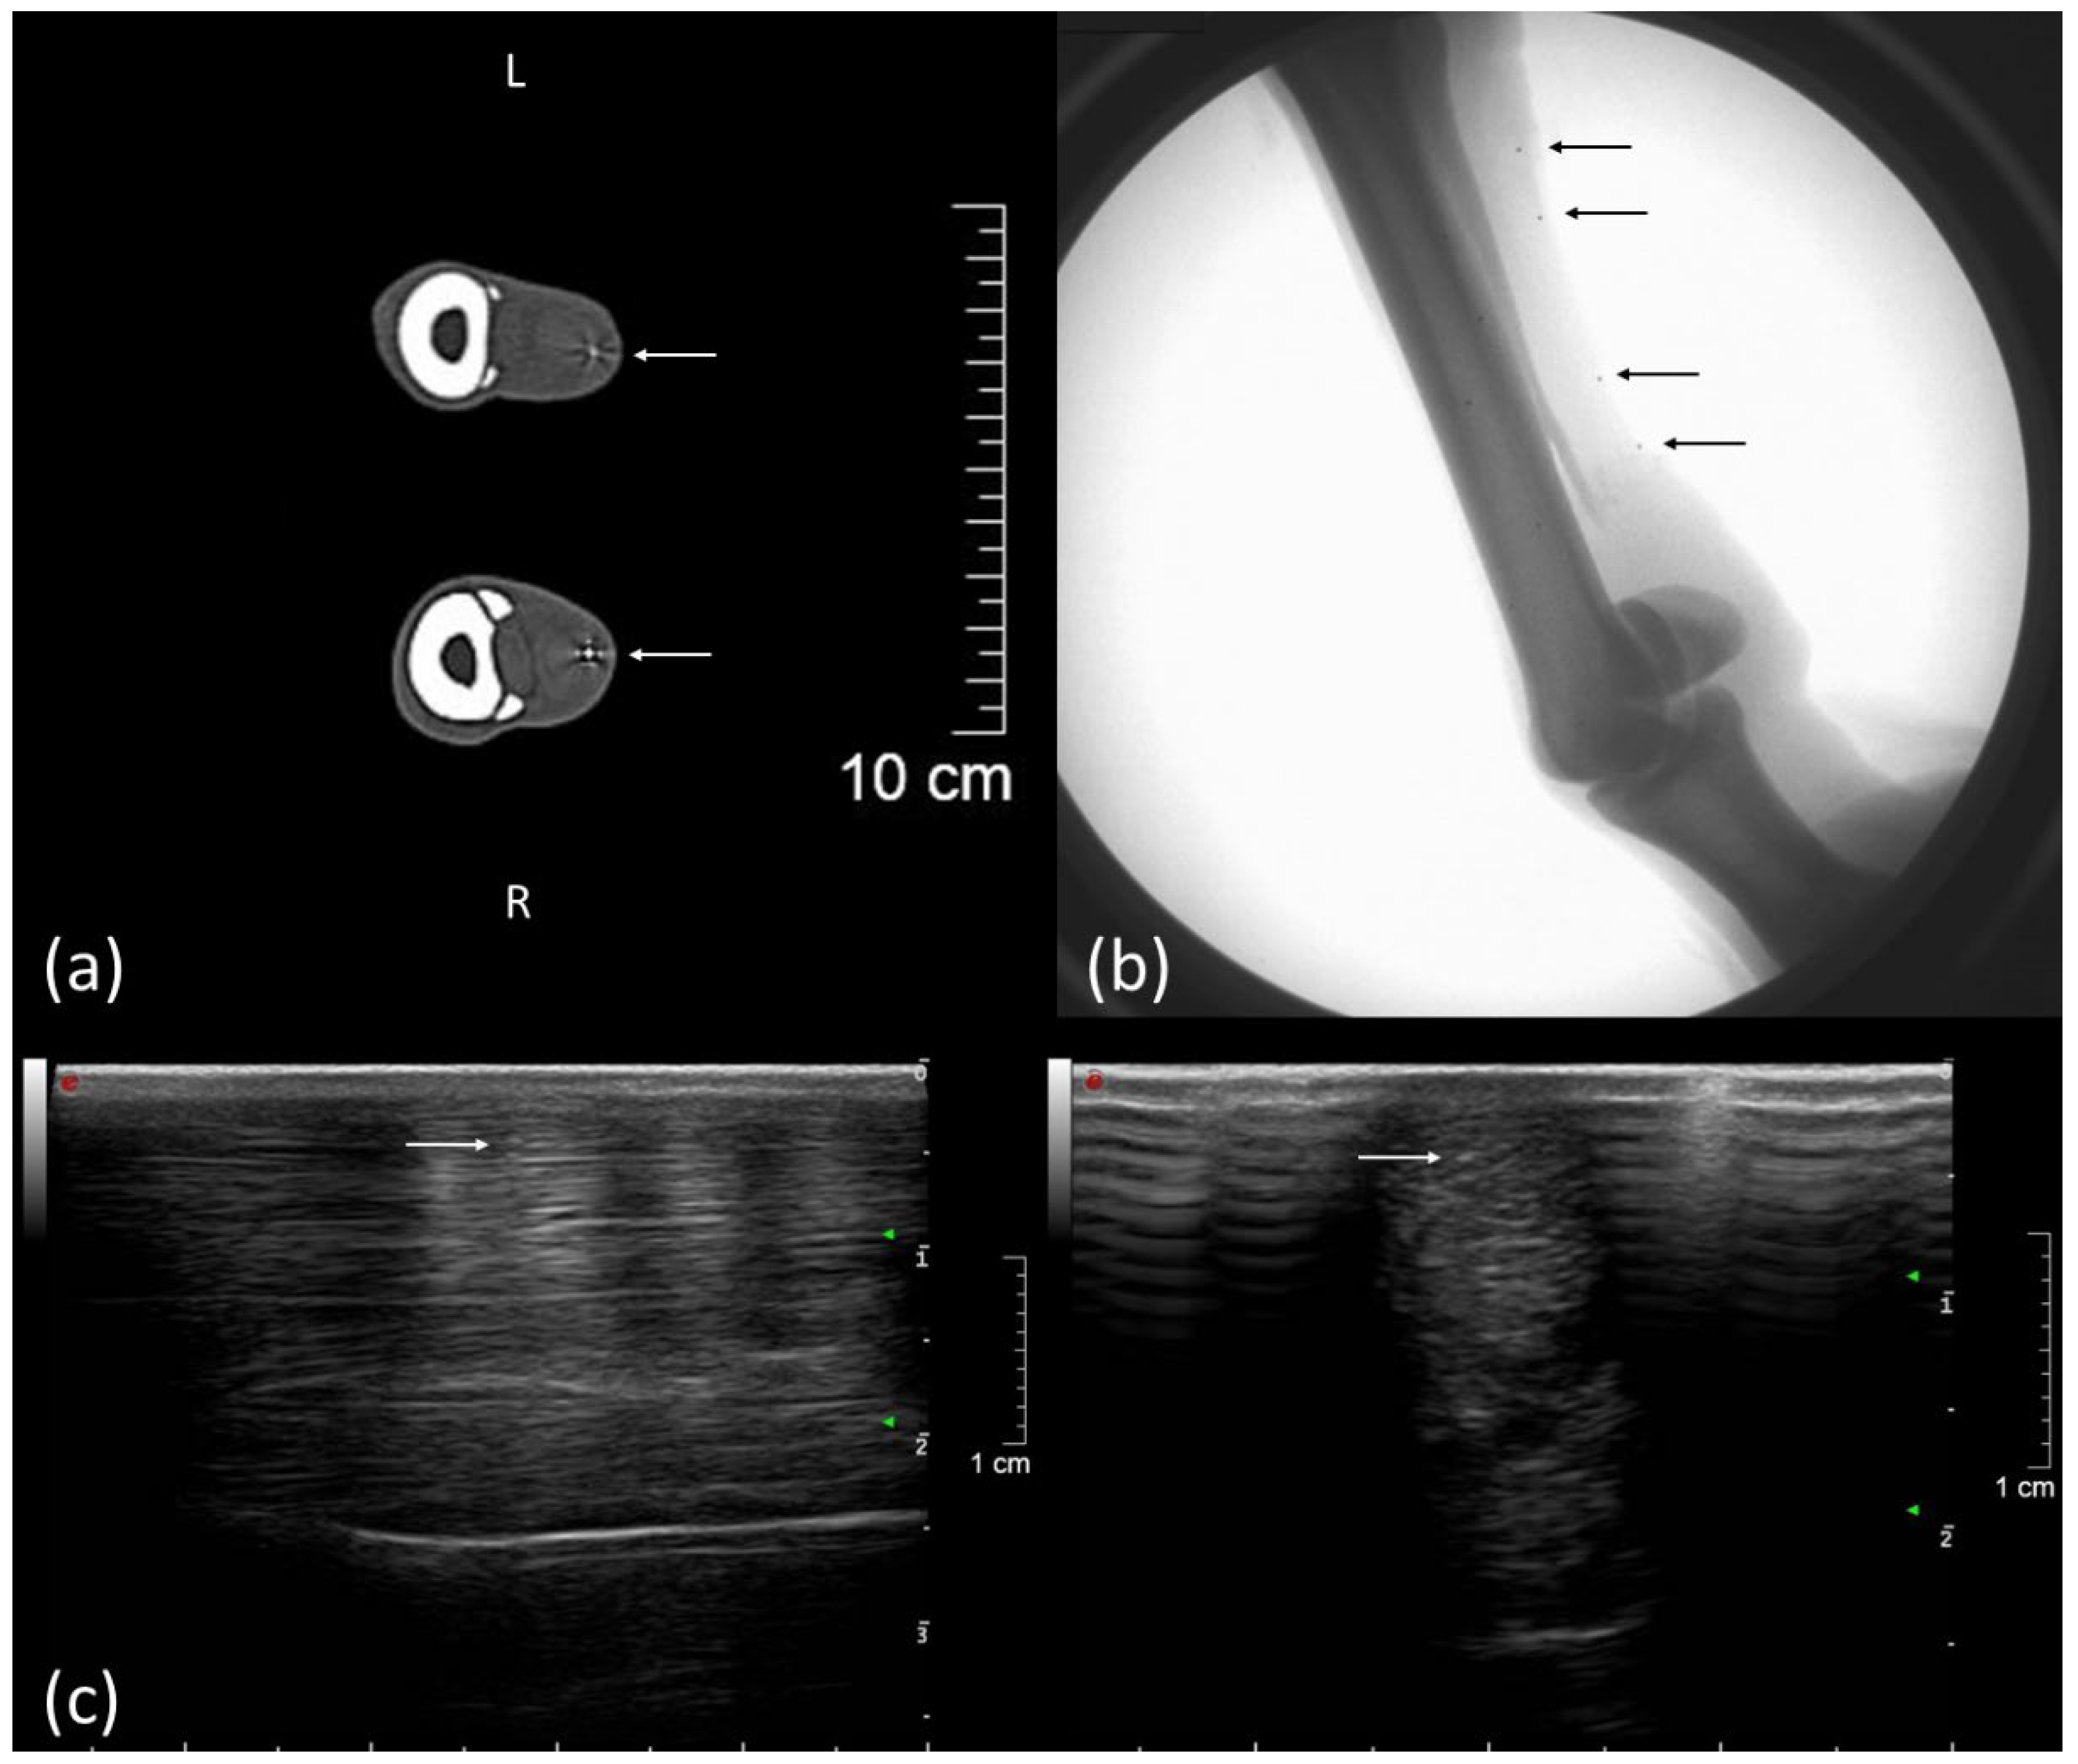

Figure 2.

Computed tomography (CT), FluoKin, and ultrasonographic images of the left forelimb of a pony with implanted tantalum beads. (a) Two tendon markers with metal streak artifact in the CT image, left is dorsal; (b) FluoKin image of the distal forelimb with four tendon markers in the SDFT and five bone markers in the third metacarpal bone; (c) longitudinal and transversal ultrasound image with acoustic shadowing and reverberation artifact due to the implanted beads, left is distal. Arrows mark the implanted beads.

Tiny tantalum beads (0.8 mm), as tendon markers in the SDFT, can be palpated at the unloaded limb without provoking a defensive movement. No pain or lameness was detected after marker implantation in the SDFTs or metacarpal bones. No inflammation of the tendon tissue, caused by the marker implantation, could be detected via ultrasound. The implanted beads could clearly be identified with ultrasound imaging and CT and in the FluoKin videos (Figure 2). The tantalum beads produced reverberation artifacts and an acoustic enhancement in ultrasound images and metal artifacts in computed tomography images.